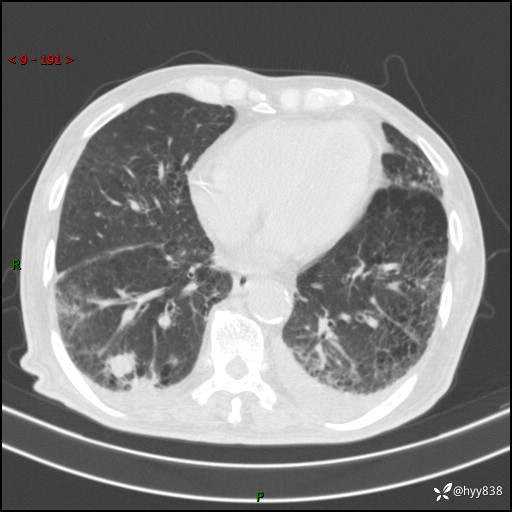

老年男性,间断咳嗽咳痰20余年,加重伴发热1天。呼吸科疑难病例讨论---结果公布

主诉:间断咳嗽咳痰20余年,加重伴发热1天

简要病史:家属代诉患者于20余年前无明显诱因出现咳嗽咳痰,痰为白色泡沫状,未行特殊治疗,不伴胸痛、胸闷、气喘、咳血等不适,1天前上午患者无明显出现发热,查体温39℃,伴咳嗽,咳痰无力,自行予以物理降温对症治疗,今晨2点左右再次出现发热,体温达40℃,自行服用复方氨酚烷胺对症治疗,凌晨3点左右复测体温38.2℃,现患者为求进一步诊治于今日就诊于我院门诊,行胸部CT提示双肺感染,遂以“肺部感染”收入我科。 患者本次起病来精神、食欲、睡眠欠佳,体力下降,体重无明显变化。

辅助检查:CT

胸部CT平扫